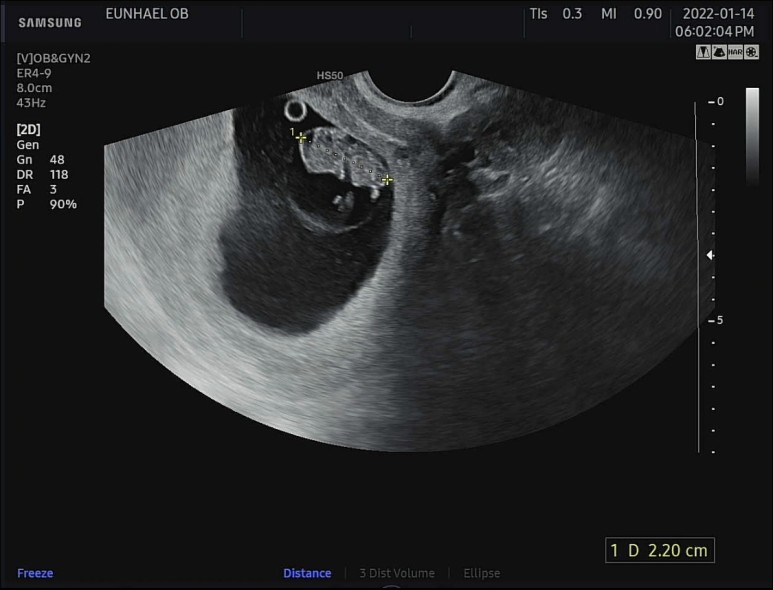

귀여운 젤리곰 보고 가세요~~

요랬던 도마뱀에서

무려 2등신의 젤리곰이 되었다 '^'!!

머리 위에 동그란 난황 도시락도 아주 야무지게 잘 가지고 있는 우리 젤리곰♡

키는 0.8cm에서 무려 1.2cm나 자란 2.2cm!